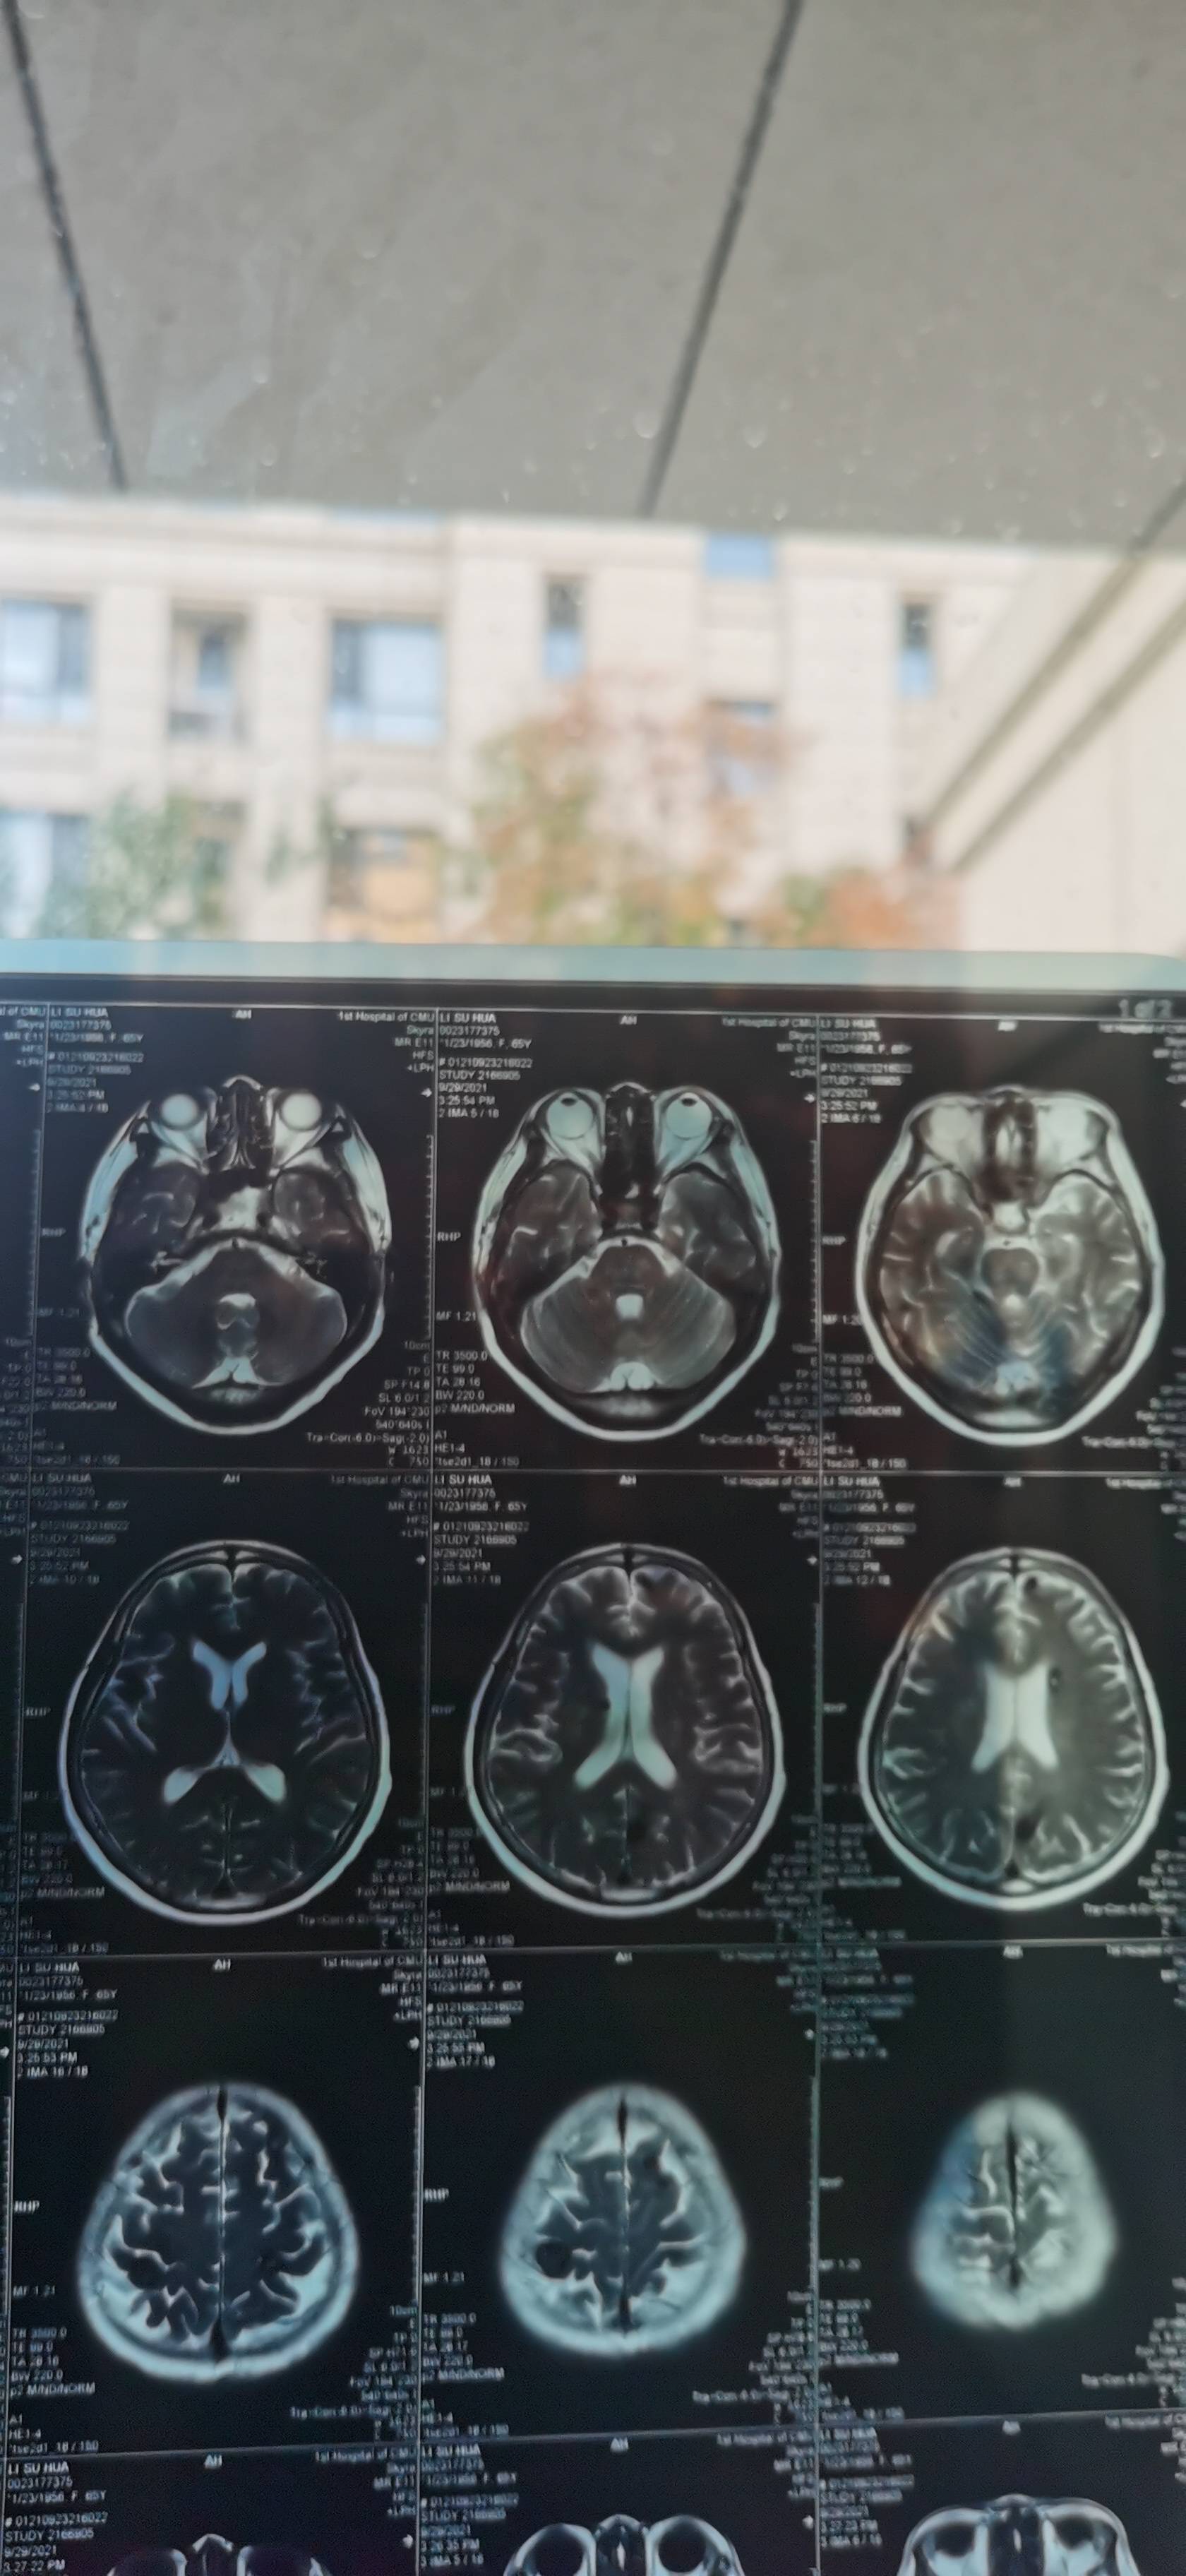

谢谢大家的建议,找到专家看片子了,专家的意见,不是脑膜转移,因为有一个肿瘤离脑干近,做射波刀的时候肯定多少有影响,而且症状也很像脑干受损,让我们观察,目前没有进展,这几天说话比之前利落了,走路不稳也有改善。

脑膜转有时在影像上很难看出,要检测脑髓液才行。